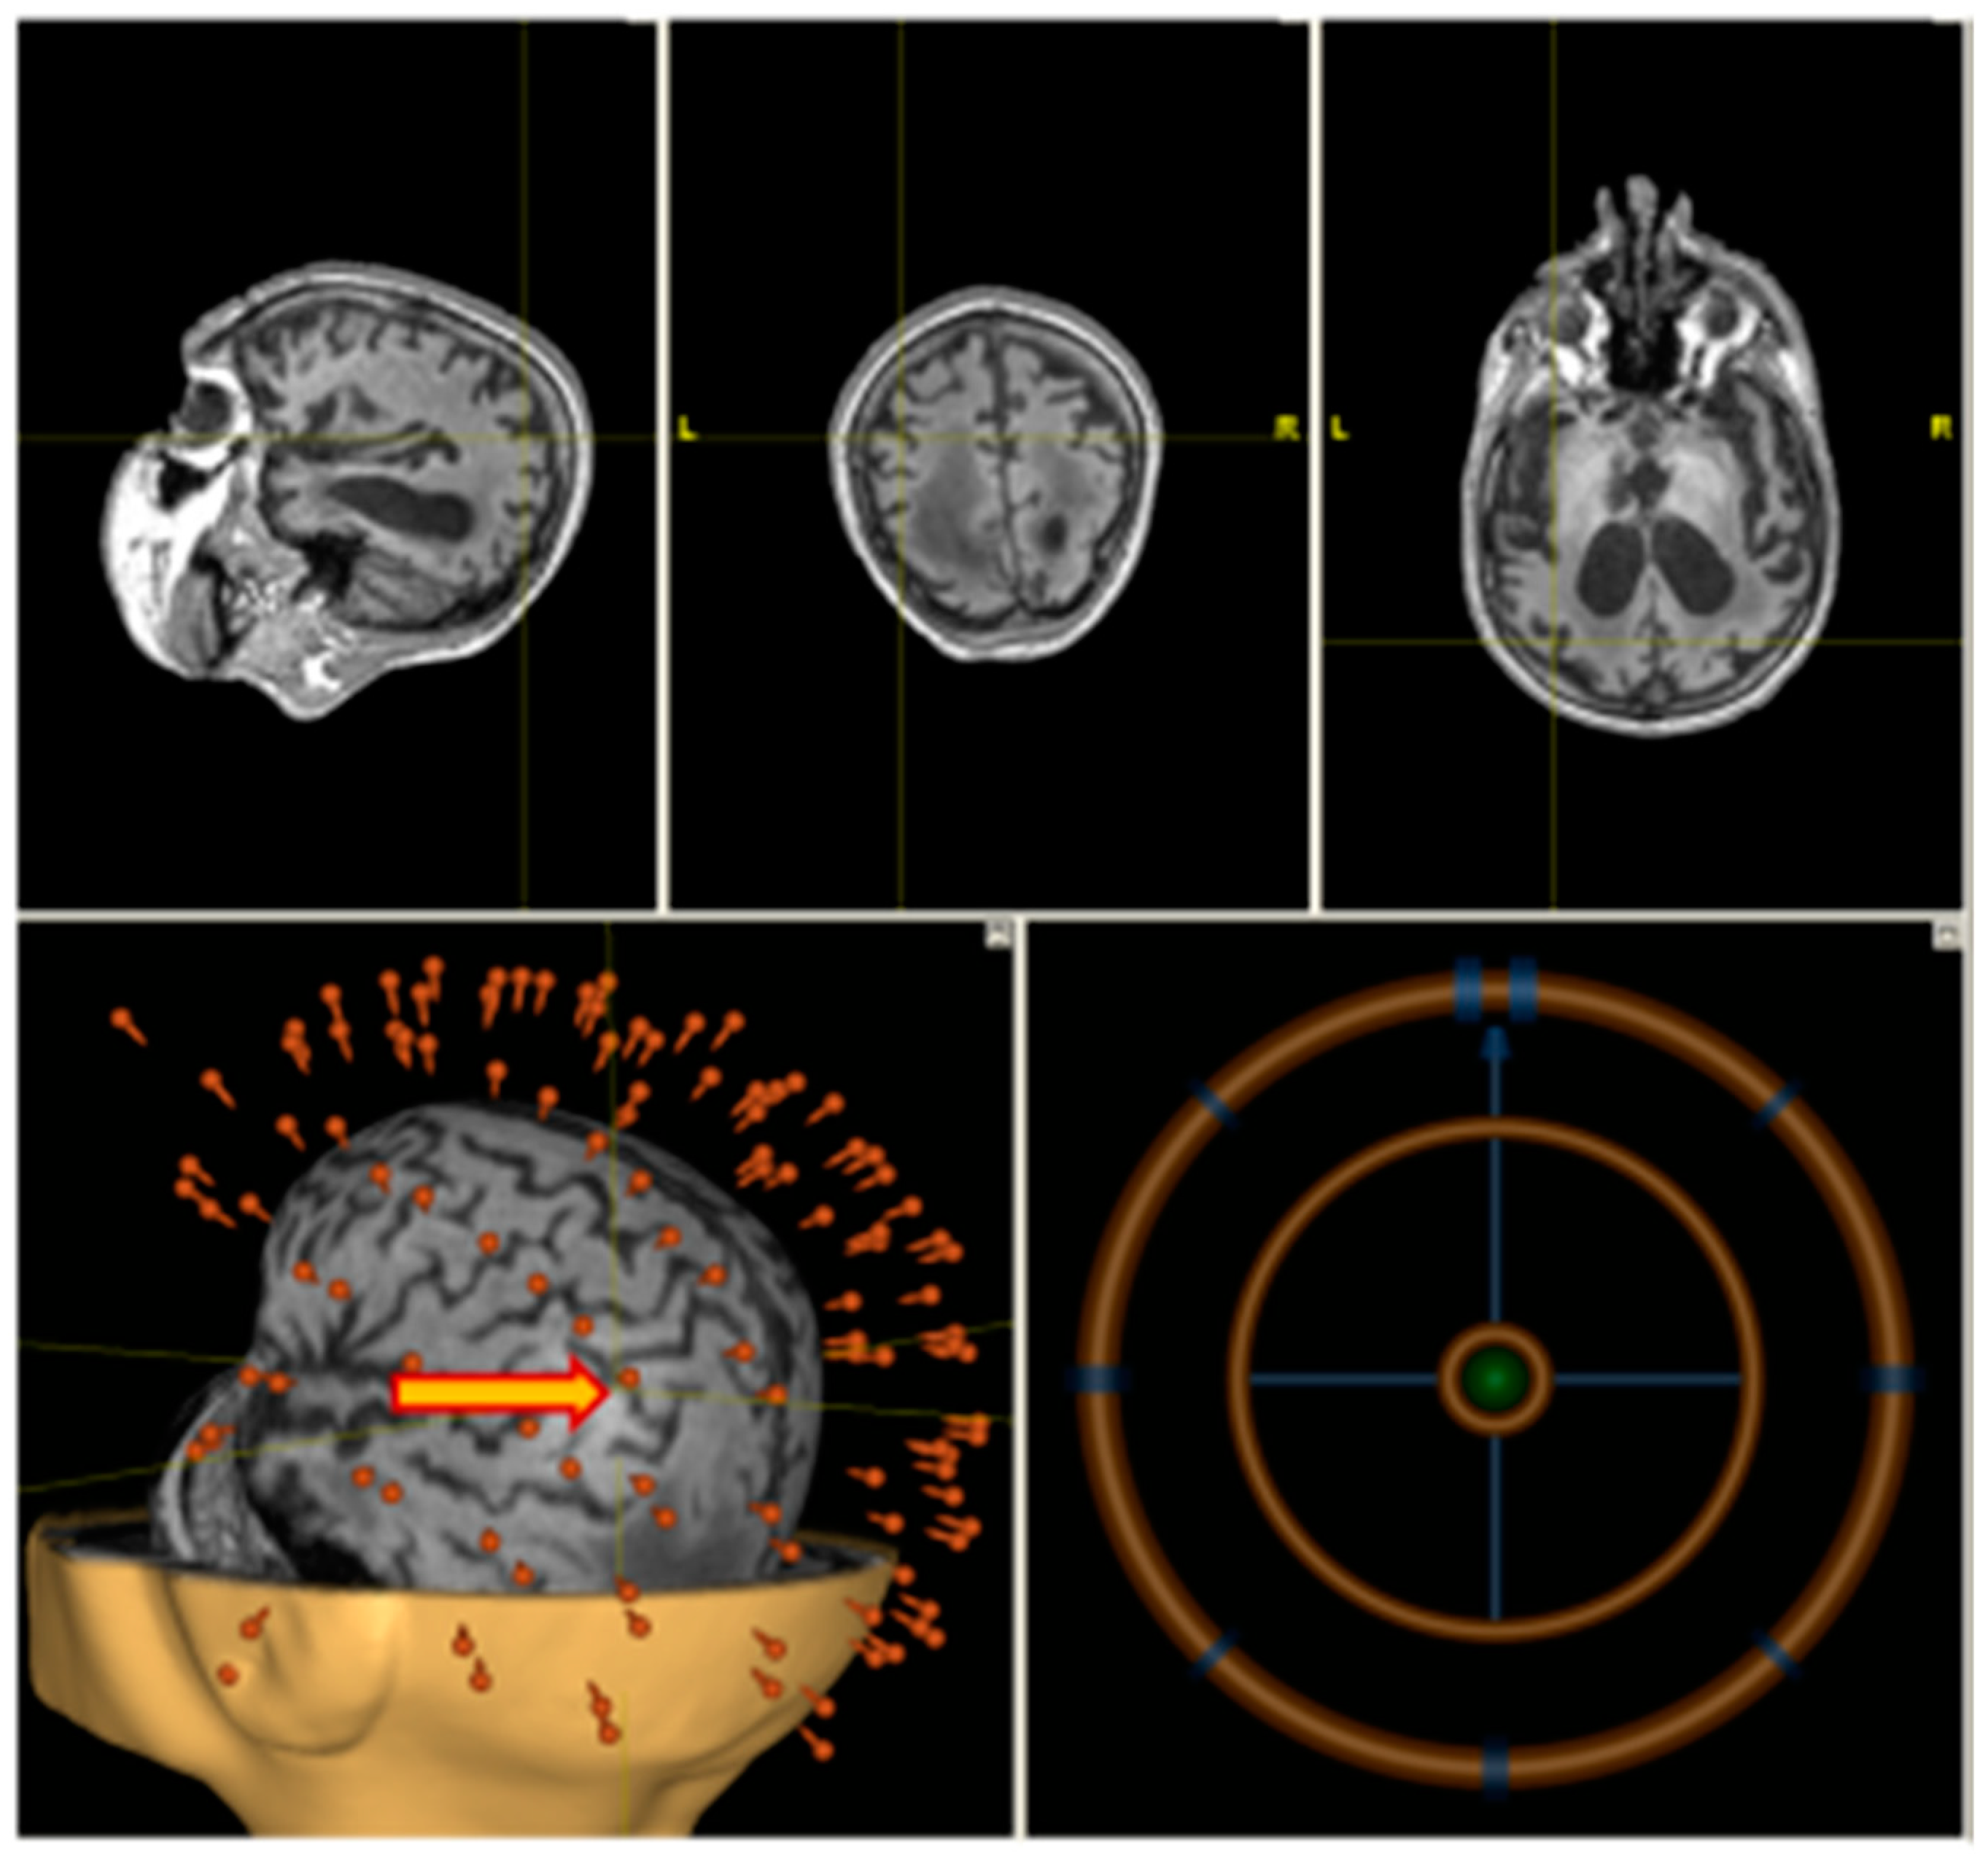

A high-resolution T1-weighted anatomical scan (MP–RAGE or SPGR) was obtained using Siemens MAGNETOM Verio 3T (Siemens AG, Muenchen, Germany) clinical scanner. A total of 176 sagittal slices were acquired to cover the whole brain. Anatomical imaging was co-registered with a patient’s head in the neuronavigation system (Nexstim Ltd., Helsinki, Finland). The stimulation point corresponding to the anatomical location over the angular gyrus was chosen individually using the T1 scan (Figure 2).

Figure 2.

Individual navigation (Nexstim) on left angular gyrus.

High frequency rTMS was delivered on a non-navigated Neurosoft stimulator (Neurosoft ltd., Ivanovo, Russia) (see Figure 2) with figure-eight coil.